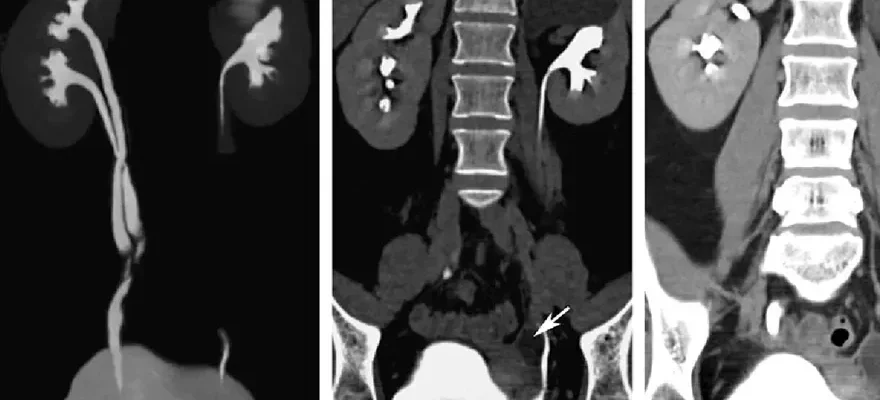

MR Ürografi, ürolojik sistemdeki çeşitli hastalıkların teşhis edilmesinde kullanılan bir görüntüleme yöntemidir. Mr ürografi bu bölgede yapılmış olan cerrahi operasyonların başarısını ölçmek için operasyon sonrası da istenebilmektedir. Bu yöntem genellikle aşağıdaki hastalıkların teşhisinde yardımcı olur:

- Üriner sistem taşları: MR Ürografi, böbrek, mesane veya idrar yollarında bulunan taşları tespit etmek ve yerlerini belirlemek için kullanılır.

- Üriner sistem tümörleri: Böbrek, mesane veya üreter gibi üriner sistemin kanserli tümörlerini teşhis etmek için bu görüntüleme yöntemi tercih edilir.

- Üriner sistem darlıkları veya tıkanıklıkları: Üreter veya üretra gibi üriner sistemdeki darlık veya tıkanıklıkların tespiti ve yerlerinin belirlenmesi için MR Ürografi kullanılır.

- Üriner sistem anormallikleri: Doğuştan gelen veya edinilmiş üriner sistem anormalliklerinin teşhisinde bu görüntüleme yöntemi önemli bir rol oynar.

MR Ürografi, üriner sisteme yönelik detaylı ve kesin bir değerlendirme sağlayarak hastalıkların tanısını koymakta ve tedavi planlamasına yardımcı olmaktadır. Tedavi planında taş, darlık, enfeksiyon ve tümörlerin yer ve büyüklükleri belirlendikten sonra tedavinin metodu belirlenmektedir.